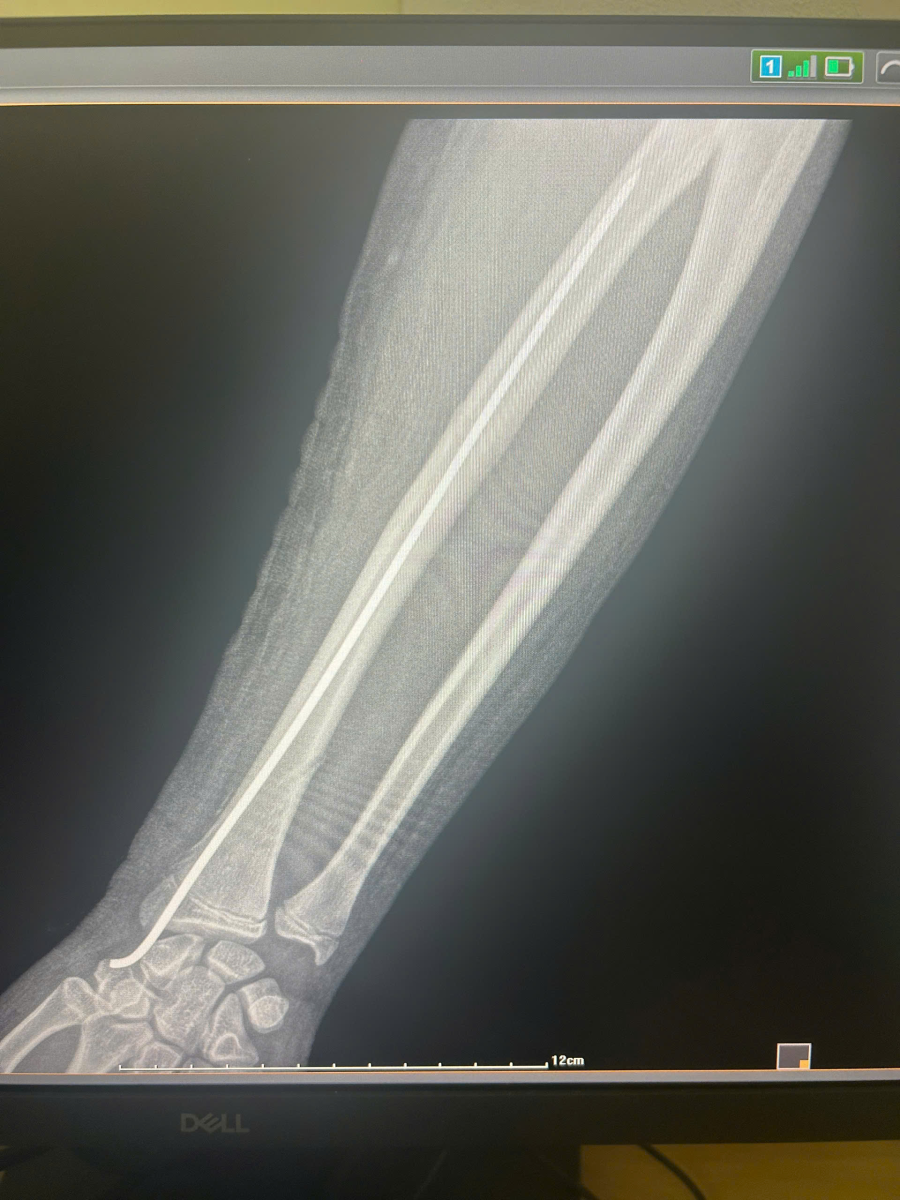

Ca phẫu thuật diễn ra thành công tốt đẹp. Hình ảnh X-quang kiểm tra sau mổ cho thấy trục xương quay đã được phục hồi hoàn toàn, đinh Kirschner nằm đúng vị trí nội tủy, cố định vững chắc ổ gãy.

Ảnh 3: Ảnh X-quang sau mổ (ghi chú: Xương đã được nắn thẳng và cố định bằng đinh nội tủy).